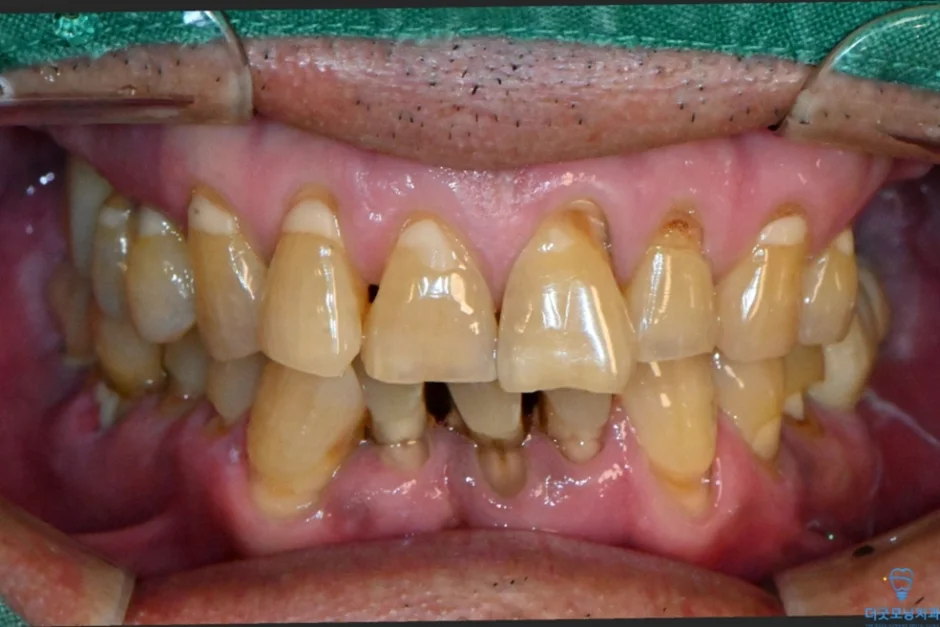

해당 환자분은 과거 치과 치료 경험이 좋지 않아 치과 공포증이 있으셨고, 치료 자체에 대한 두려움이 크셨습니다. 치료를 오랫동안 미루셨고, 그 사이 구강 상태가 많이 악화된 상태로 내원하셨습니다.

먼저 파노라마 엑스레이와 CT를 통해 구강 전체 상태를 확인하였습니다.